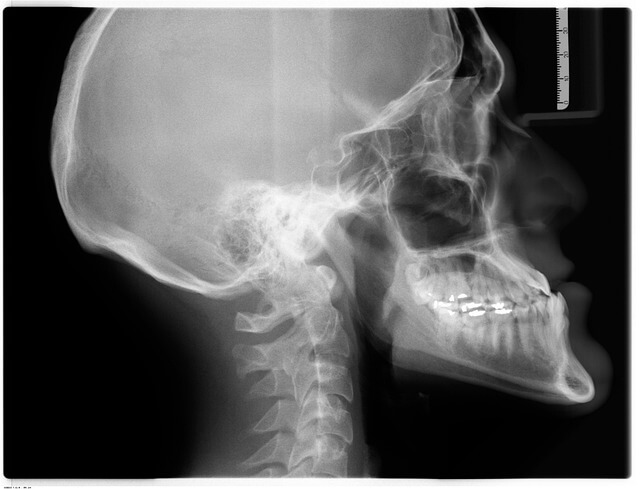

부정교합은 턱이 닫혔을 때 치아의 정렬이 잘못되거나 위치가 잘못되는 것을 말합니다. 부정교합에는 다양한 분류가 있으며, 일반적으로 정렬의 본질과 심각성에 따라 분류됩니다. 한 가지 일반적인 분류 체계는 Edward Angle 박사에 의해 개발된 분류 체계입니다. 이 체계는 부정교합을 세 가지 주요 분류로 분류합니다. 첫째, Class I 부정교합은 위턱의 첫 번째 어금니는 아래턱의 첫 번째 어금니와 함께 교합하는 경우입니다. 다른 치아들은 제대로 정렬되어 있을 수 있지만, 삐뚤 비뚤 하거나, 간격을 두거나, 또는 회전된 치아가 있을 수 있습니다. 둘째, Class II 부정교합은 위쪽 제1 어금니는 아래쪽 제1 어금니에 앞으로(앞쪽에 더 가깝게) 교합되는 경우입니다. Class II 부정교합은 Class II Division 1(상악 절치의 돌출)Class II Division 2 (상악 절치의 후퇴)로 다시 세분됩니다. 셋째, Class III 부정교합은 위쪽 첫 번째 어금니는 뒤쪽에서 아래쪽 첫 번째 어금니와 교합되는 경우입니다. Class III 부정교합을 underbite라고 부르기도 합니다. 부정교합을 진단하고 치료 계획을 세우기 위해 이런 분류들을 사용합니다.